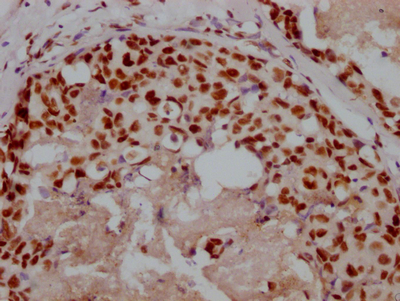

The image on the left is immunohistochemistry of paraffin-embedded Human brain tissue using CSB-PA297945(KRT13 Antibody) at dilution 1/35, on the right is treated with fusion protein. (Original magnification: ×200)

The image on the left is immunohistochemistry of paraffin-embedded Human cervical cancer tissue using CSB-PA297945(KRT13 Antibody) at dilution 1/35, on the right is treated with fusion protein. (Original magnification: ×200)